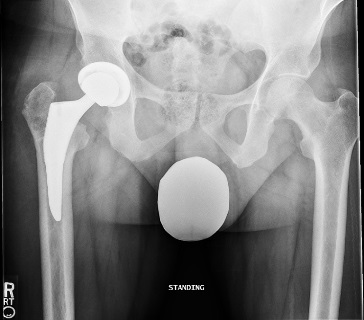

Postoperative radiographs were satisfactory: